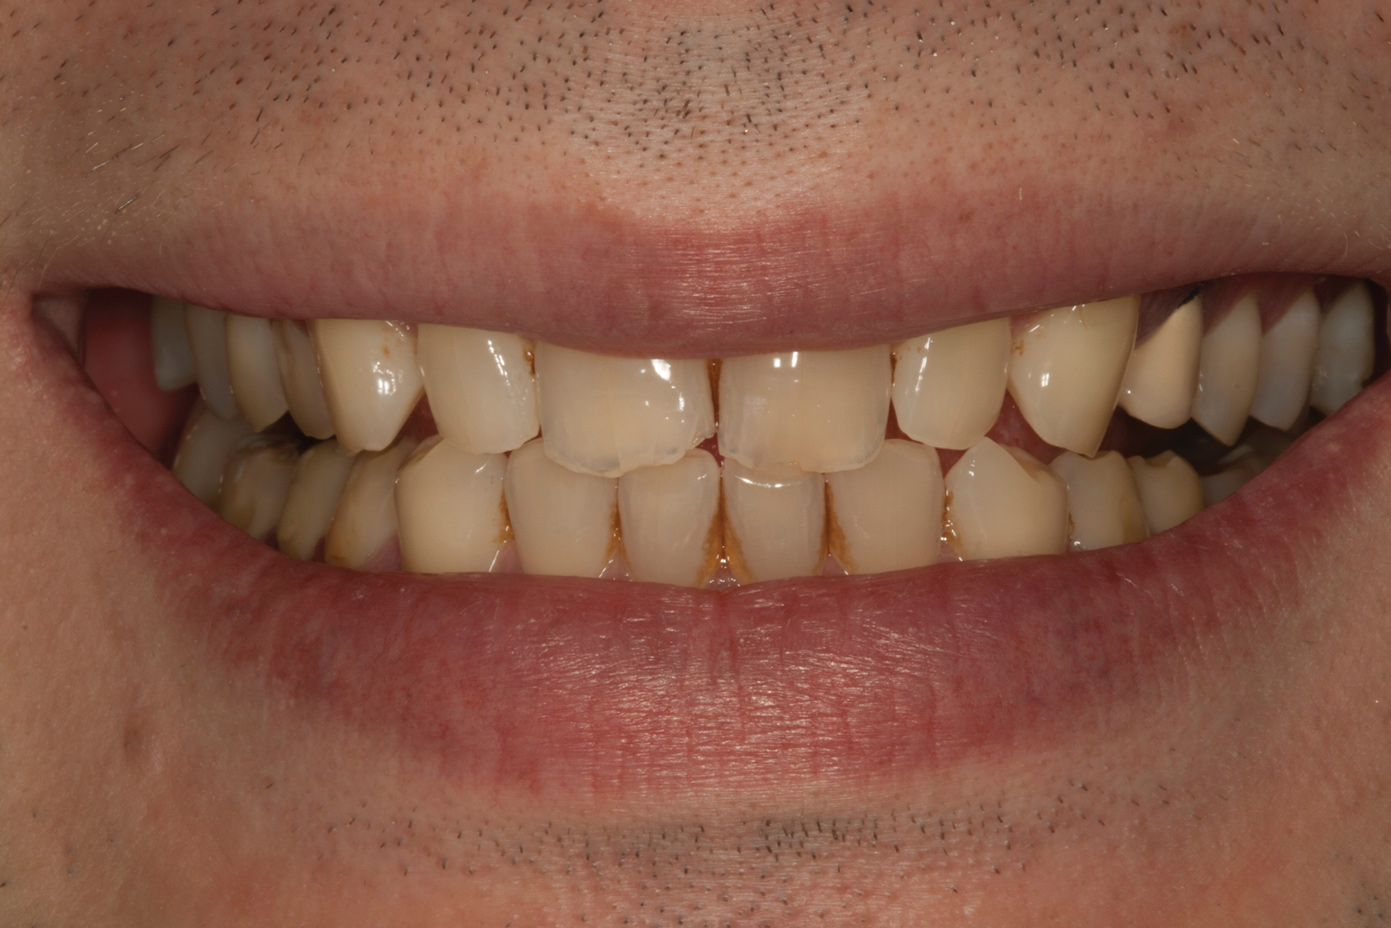

A 34-year-old male patient with no medical issues presented to the office with the chief complaint of a failing crown on tooth No. 12. The patient was also unhappy with his bite and the appearance of his teeth (Figure 1 and Figure 2).

The dentofacial examination revealed a low smile line with no incisor display when the lips were in repose. The anterior teeth were chipped and worn, and their overall color was darkened. The buccal corridors were deficient, and the failing crown on tooth No. 12 was visible in a full smile.

Fig 1. Preoperative smile photograph.

Figure 1